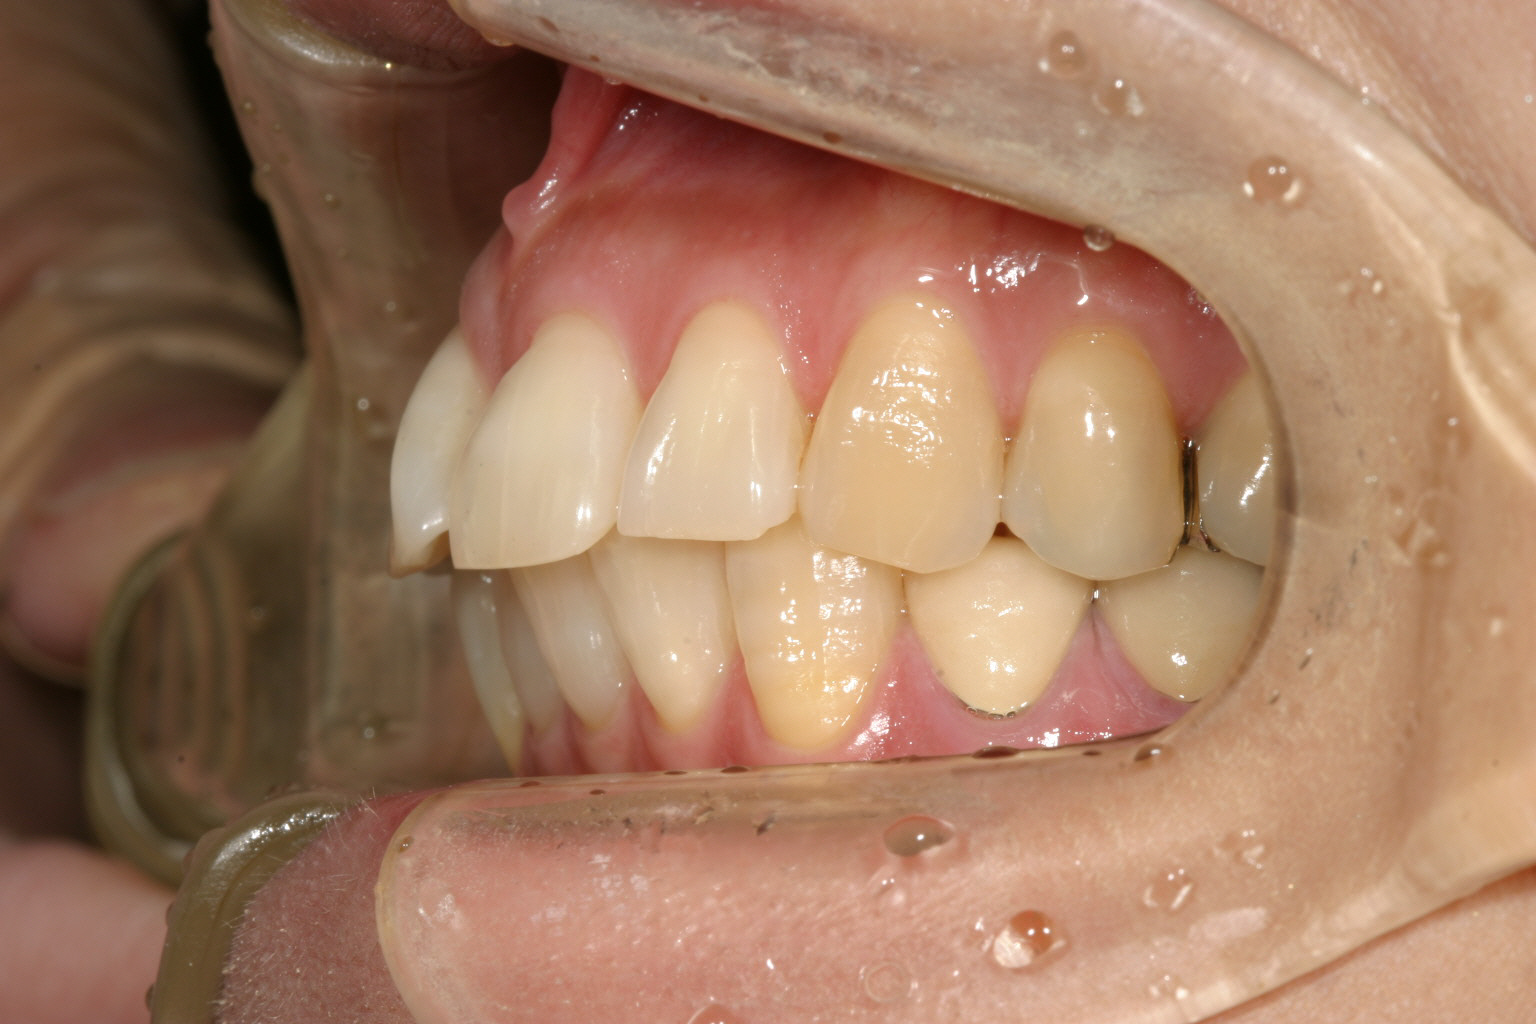

多少の過度なオーバージェットが認められます。

側面観はオーバージェットも改善してます。